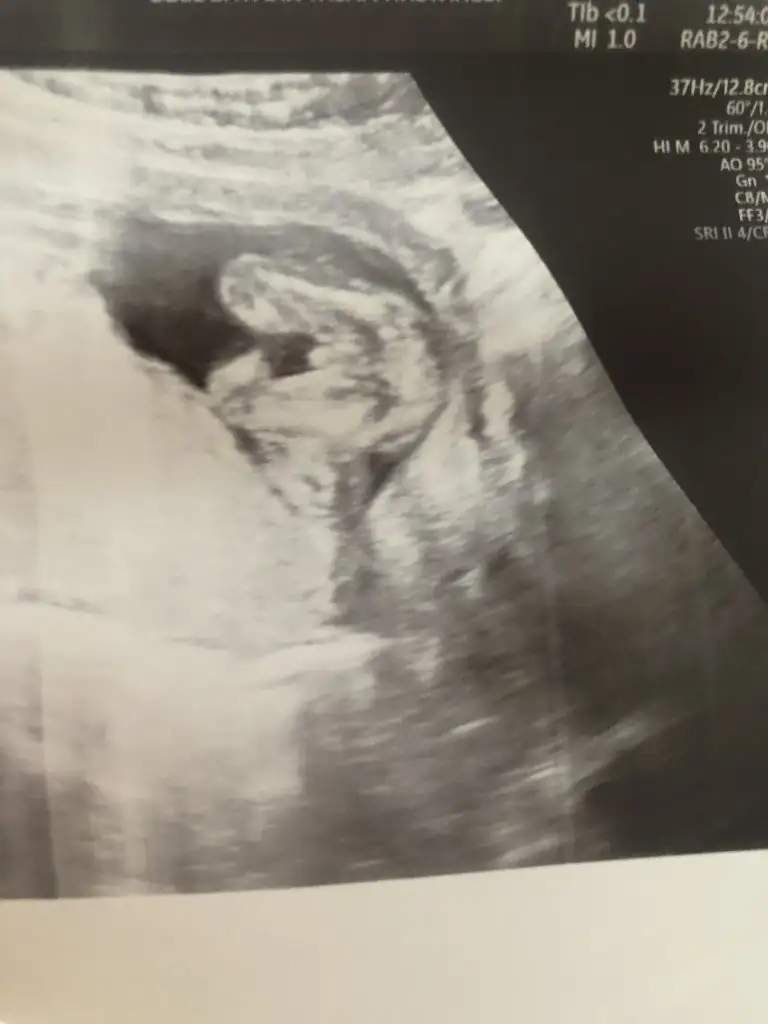

Yok daha gostermedi ki, ufak yaramaz. Mideme oturdu, midem çatliyorrr.

Ben Rusyadayim, burda yasiyorum. Burda 4 ayindan önce soylemiyorlar. Ama bizde yani Azerbaycanda gorunuyorsa direk 3 ayindan soyluyirlar. Burda yasak. Gorselerde 4 aya kadar bekliyorlar. Bende meraktan catliyorum.